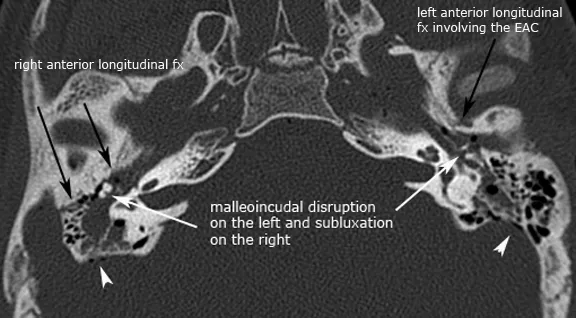

| Temporal bone fracture | <4 hours | 5-10% | 60-90% hearing | Battle's sign |

Temporal Bone Fracture Complications (<2 hour imaging window)